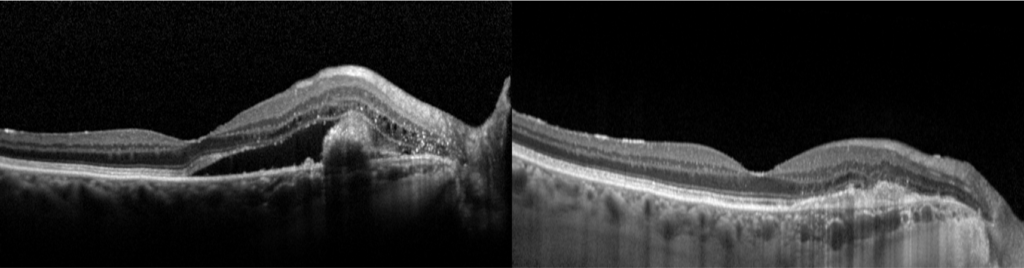

L’OCT* (Tomographie par Cohérence Optique) permet de visualiser en coupe les différentes couches de la rétine, la présence de liquide intra ou sous rétinien. L’angiographie à la fluorescéine* et au vert d’indocyanine* permet de localiser les polypes, les différents points de fuite, et la présence de néovaisseaux anormaux.

Coupe comparative en OCT : avant (image de gauche) et après (image de droite) traitement combiné par PDT demi fluence et IVT d’anti VEGF. Disparition du flux intra rétinien et occlusion du polype inter papillo maculaire